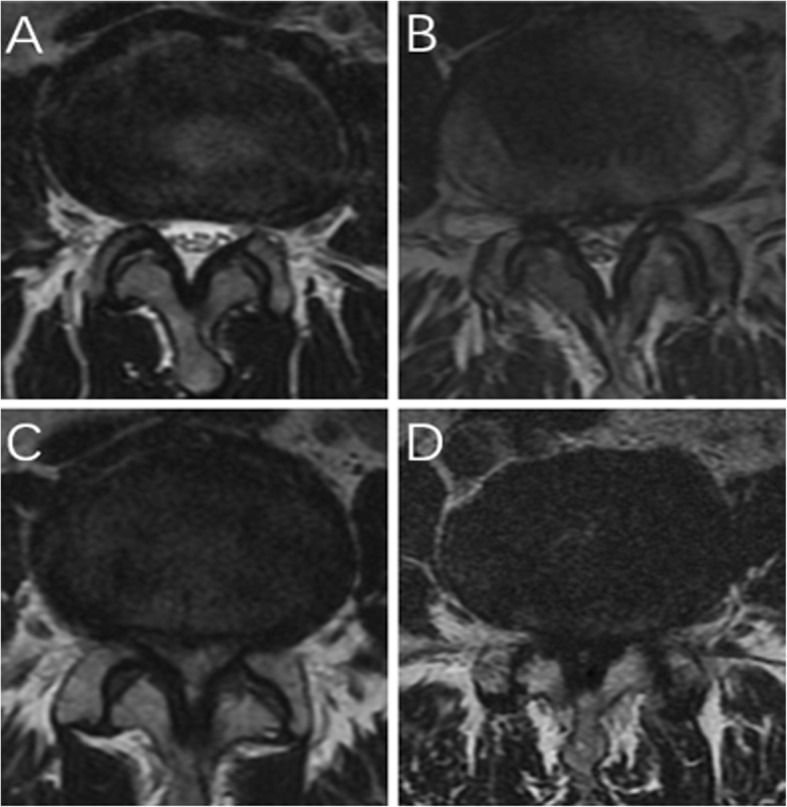

The inclusion criteria were as follows: one to three level degenerative LSS; back and/or leg pain refractory to conservative treatment for at least 6 weeks; LSS of grades B to D based on the morphological characteristic in magnetic resonance imaging (MRI, Fig. 1) [11–13]; and lateral recess stenosis of grades 2–3 in MRI (Fig. 2) [14, 15]. The exclusion criteria included LSS with disc protrusion or prolapse, acute spinal fracture, infection, tumor, revision, spondylolisthesis, and scoliosis (cobb > 20°).

Fig. 1.

Classification of LSS. a Grade A: no or minor stenosis; there is clearly CSF visible inside the dural sac. b Grade B: moderate stenosis; the rootlets occupy the whole of the dural sac, but they can still be individualized. Some CSF is still present giving a grainy appearance to the sac. c Grade C: severe stenosis; no rootlets can be recognized, the dural sac demonstrating a homogeneous gray signal with no CSF signal visible, and there is epidural fat present posteriorly. d Extreme stenosis; in addition to no rootlets being recognizable, there is no epidural fat posteriorly